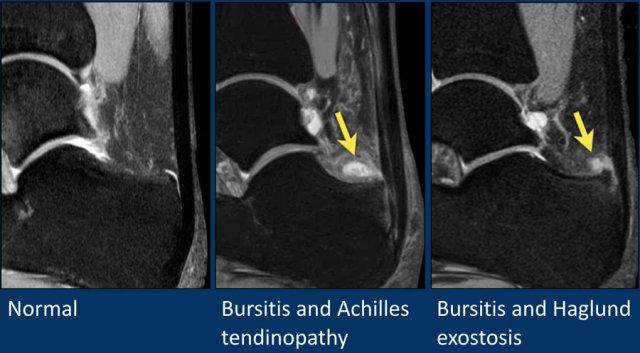

Bình thường, có thể thấy một lượng nhỏ dịch trong túi hoạt dịch sau gót (retrocalcaneal bursa).

Lượng dịch quá nhiều là dấu hiệu của viêm túi hoạt dịch (bursitis).

Dày gân Achilles được ghi nhận trong viêm cận gân (paratenonitis).

Hội chứng Haglund bao gồm bộ ba triệu chứng:

- Gai xương Haglund (Haglund’s exostosis)

- Viêm túi hoạt dịch sau gót (Retrocalcaneal bursitis)

- Bệnh lý gân Achilles tại điểm bám (Achilles insertional tendinopathy)